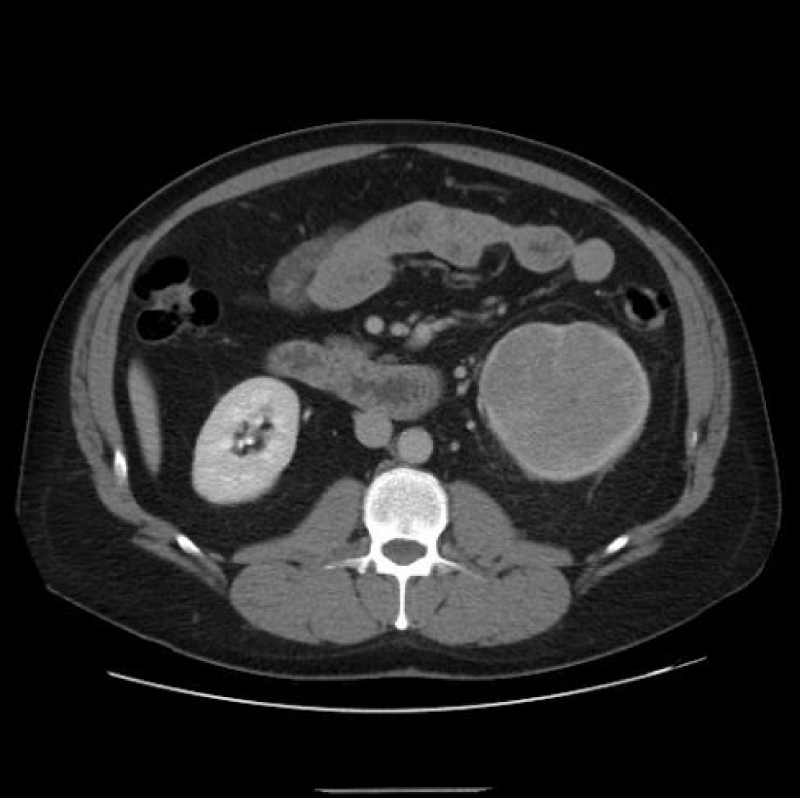

For evaluating SRM (Figure 3), thin CT slices of 2 mm to 3 mm are preferred to demonstrate lesion extent, hence minimizing ‘partial volume artifacts.’ This allows in both the coronal and sagittal planes, post-processing high-resolution Three-Dimensional multiplanar reconstructions (MPR). Maximum intensity projection (MIP) imaging processing tool projects the voxels of the highest attenuation into a Two-Dimensional image. This is especially useful post-operatively, where cortical profiles and the integrity of blood vessels may be evaluated [1,6].

Download Image

Figure 3: Right renal mass measuring 2 cm.